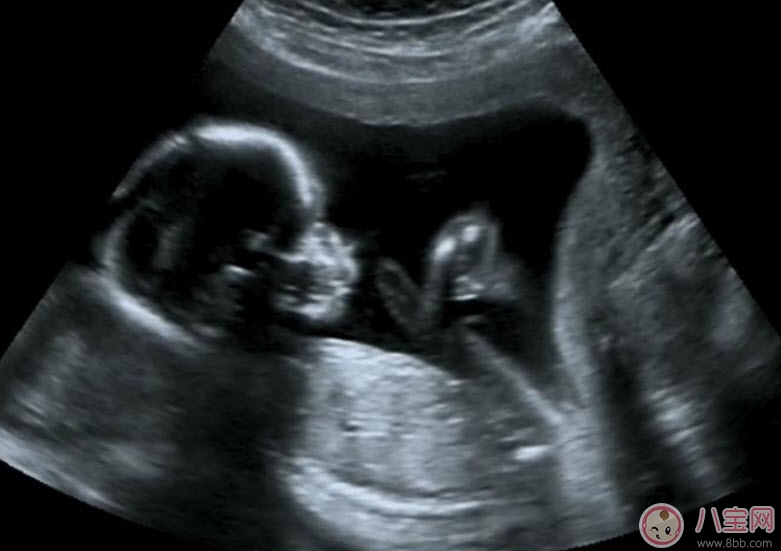

B超既可以測量胎兒的各個部位,如胎頭大小、胎臀長度,也可以用于在早期妊娠來測定胎兒的具體懷孕時間(醫學上叫做孕周),測定胎頭的雙頂徑、頭圍、腹圍及胎兒股骨的長度等,這些數據可以判斷胎兒的生長發育情況。

B超能夠直觀胎兒在母體內的活動狀況,諸如呼吸情況、胎兒的運動、整個身體大的運動、肢體的運動、胎兒的吞咽動作等等,可以一覽無余。之外,通過觀察胎兒的張力是否良好,可以判斷胎兒在宮內是否缺氧或者受到損害,準確預報胎兒安危。